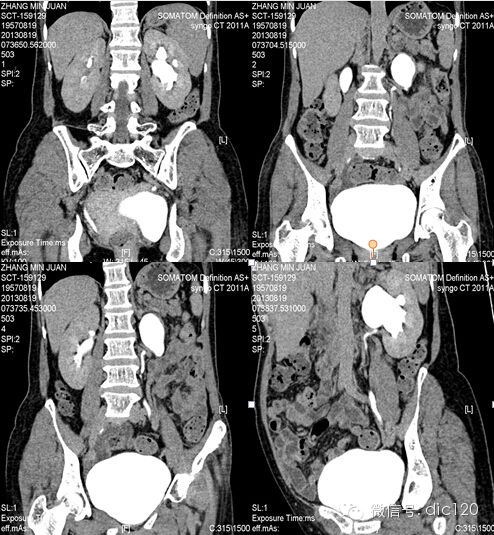

F,56Y,左腰腹部疼痛3天,B超:左肾积水,左输尿管上段扩张。

结果:卵巢静脉综合征,患者有外压性输尿管梗阻,卵巢静脉与输尿管交叉处有粘连。